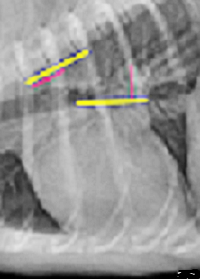

September 2025 article, Turkish cardiologists Murat Vurucu

(right), Aykut Cokogullu, and Bugra Ozcan performed open heart

mitral valve repair surgery on a cavalier King Charles spaniel in heart

failure with severe mitral regurgitation. The dog's pre-operative vitals

included vertebral heart score (VHS) of 15.0, left atrial-to-aortic root

ratio (LA/Ao) of 2.87, and left ventricular internal diameter in

diastole (LVIDd) of 46.1 mm. They performed semi-circular suture

annuloplasty and chordal reconstruction using ePTFE sutures. Artificial

chordae lengths were adjusted using a modified taut-line hitch (TLH)

knot technique. The taut-line hitch (left) is a nautical knot

with an adjustable loop for lines under tension. It can be re-adjusted

periodically to maintain

tension

and is particularly useful in setting the proper tension of a series of

chordae supporting the mitral valve during repair surgery. The surgery

was successful, and 3 months post-surgery vitals were reduced to VHS =

12.0, LA/Ao = 1.78, and LVIDd = 33.3 mm. At the long-term follow-up a

year later, no clinical signs of congestive heart failure were observed.